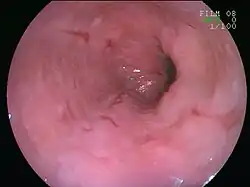

An esophageal ulcer visualized by esophagoscopy: the reddened area at 10 o'clock on the surface of the mucosa.

An upper endoscopy is a procedure to look at the esophagus by using an endoscope. While looking at the esophagus, the doctor is able to take a small biopsy. The biopsy can be used to confirm inflammation of the esophagus.